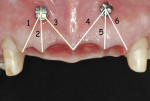

A piezosurgical unit (Mectron s.p.a, www.mectron.com) and tips were used for the osteotomies. A special caliper with the shape and dimensions of the titanium bars was used to verify the size of the osteotomies. The titanium bars carried into place by pliers were seated into the sites (Figure 9) before being pushed deeply with a chisel and surgical mallet. As a result, all titanium bars obtained primary stability (Figure 10).

The sites were then covered with granulated osteoconductive material (Bio-Oss®, Geistlich Pharma AG, www.geistlich-na.com) and strips of resorbable membranes (Bio-Gide®, Geistlich Pharma AG). The flap was then sutured with a 4-0 Vicryl Plus thread (Johnson and Johnson Intl., www.jnj.com).

Data Recording

One month after the extractions with insertion of the provisional fixed partial denture, measurements were recorded to assess changes in papilla height over time. Two orthodontic transcortical titanium screws (Spider Screw®, Ortho Technology, www.orthotechnology.com) were symmetrically inserted apically between teeth Nos. 7-8 and 9-10, respectively. These screws served as reference points. The distance was measured with a digital caliper (Mitutoyo America Corp., www.mitutoyo.com) from the center of the head of the spider screw to the tip of each papilla (Figure 13).

Distances (D) were measured in six different locations at 1 month (baseline-T0), 6 months from baseline (T1), and 12 months from baseline (T2) (Figure 14). All measurements began 5 minutes after removal of the provisional fixed partial denture. Each value was the mean of three measurements for each papilla made by three different blind operators. Mean distances (D) are reported in Table 1.